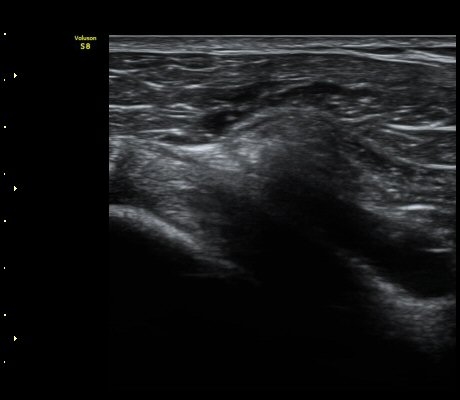

¿À±¸µ¹±â Ⱦ´Ü¸é°Ë»ç»ó ¿Áµ¹±â ¾Æ·¡, ³»Ãø, °ß°©ÇÏ±Ù°Ç Ç¥Ãþ¿¡¼­ ¼ö¾×Àú·ù°¡ °üÂûµÈ´Ù

(±×¸² 3, 4).